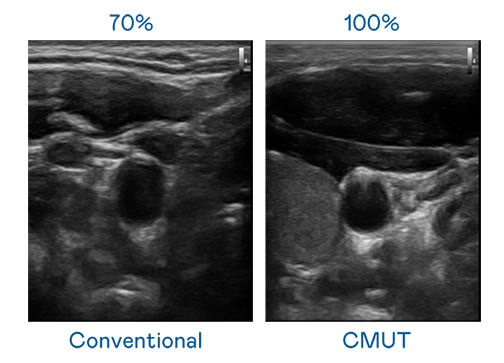

CMUT 技术是一种用电容式微机电元件来产生超音波讯号的技术。与传统 PZT 压电式技术相比,CMUT 频宽增加 30%,更宽频的超音波讯号让影像解析度大幅提升,是实现高影像品质医疗超音波扫描、促进精准医疗发展的关键技术。

超音波影像的解析度高低,首先取决于探头能发出的讯号频宽。凯发k8官方网站登录 CMUT 可提供高清晰的超音波讯号,提供高频宽、高灵敏度、影像纹理细节更高的超音波影像,协助医护人员缩短影像判读时间及利用精准的医疗影像进行诊断。